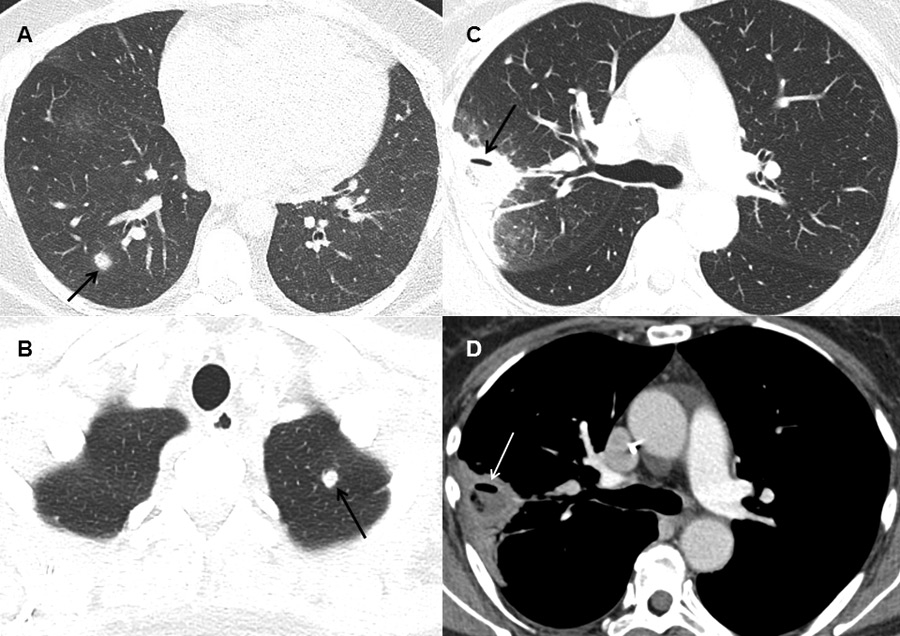

Typical findings on computed tomography.

(A) Dense, well-circumscribed lesion with a halo (arrow) in the right lower lobe in a patient with possible invasive fungal infection (IFI) (B) Dense, well-circumscribed lesion in the left upper lobe (arrow) in a patient with possible IFI (C and D) Dense lesion with an air-crescent sign (arrows) in the right upper lobe in a patient with proven IFI (mucorales spp.).